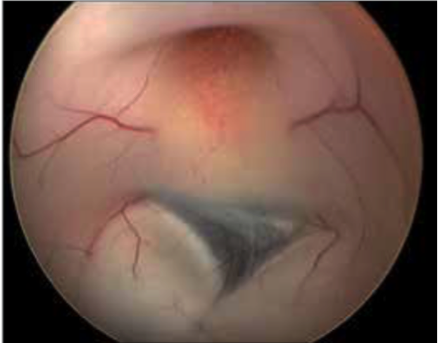

Bei dem Endoskop handelt es sich um ein optisches Lichtleitungssystem, an das eine Kamera angeschlossen ist. Darüber hinaus ist es mit einem Spül- und Arbeitskanal zum Einbringen von Miniaturinstrumenten wie Fasszangen, Ultraschallsonden oder Ballonkathetern ausgestattet.  Der Operationszugang ist über einen bleistiftdünnen Kanal möglich. Die Kamera ermöglicht es, gestochen scharfe Bilder in Full-HD-Qualität aus verschiedenen Perspektiven auf einen hoch auflösenden Bildschirm zu übertragen. Verschiedene Winkeloptiken ermöglichen die umfassende Inspektion aller Bereiche. Das verschafft dem Operateur einen detailreichen Blick auf das Operationsfeld mit seinen empfindlichen Strukturen wie Blutgefäßen oder Nerven, wodurch die Operationssicherheit gesteigert wird.

Uns stehen drei Endoskopie-Systeme zur Verfügung. Eines dient der transventrikulären Endoskopie. Dieses Instrument wird durch den Ventrikel (Nervenwasserkammer) eingeführt und zur Entfernung von Tumoren, zur Herstellung von Verbindungen innerhalb der Nervenwasserkammer und zu den Räumen außerhalb des Gehirnes, aber auch zur Probeentnahme von Tumoren, die neben der Mittellinie liegen, genutzt.

Tumoren und Zysten in den Hirnkammern können über ein kleines Bohrloch im Schädel so oft sicher und schonend entfernt werden. In Kombination mit modernster Neuronavigation und intraoperativer Bildgebung kann sich der Chirurg genau im OP-Gebiet orientieren und das Endoskop exakt positionieren. Das sind optimale Voraussetzungen für die Behandlung hochkomplexer Erkrankungen.